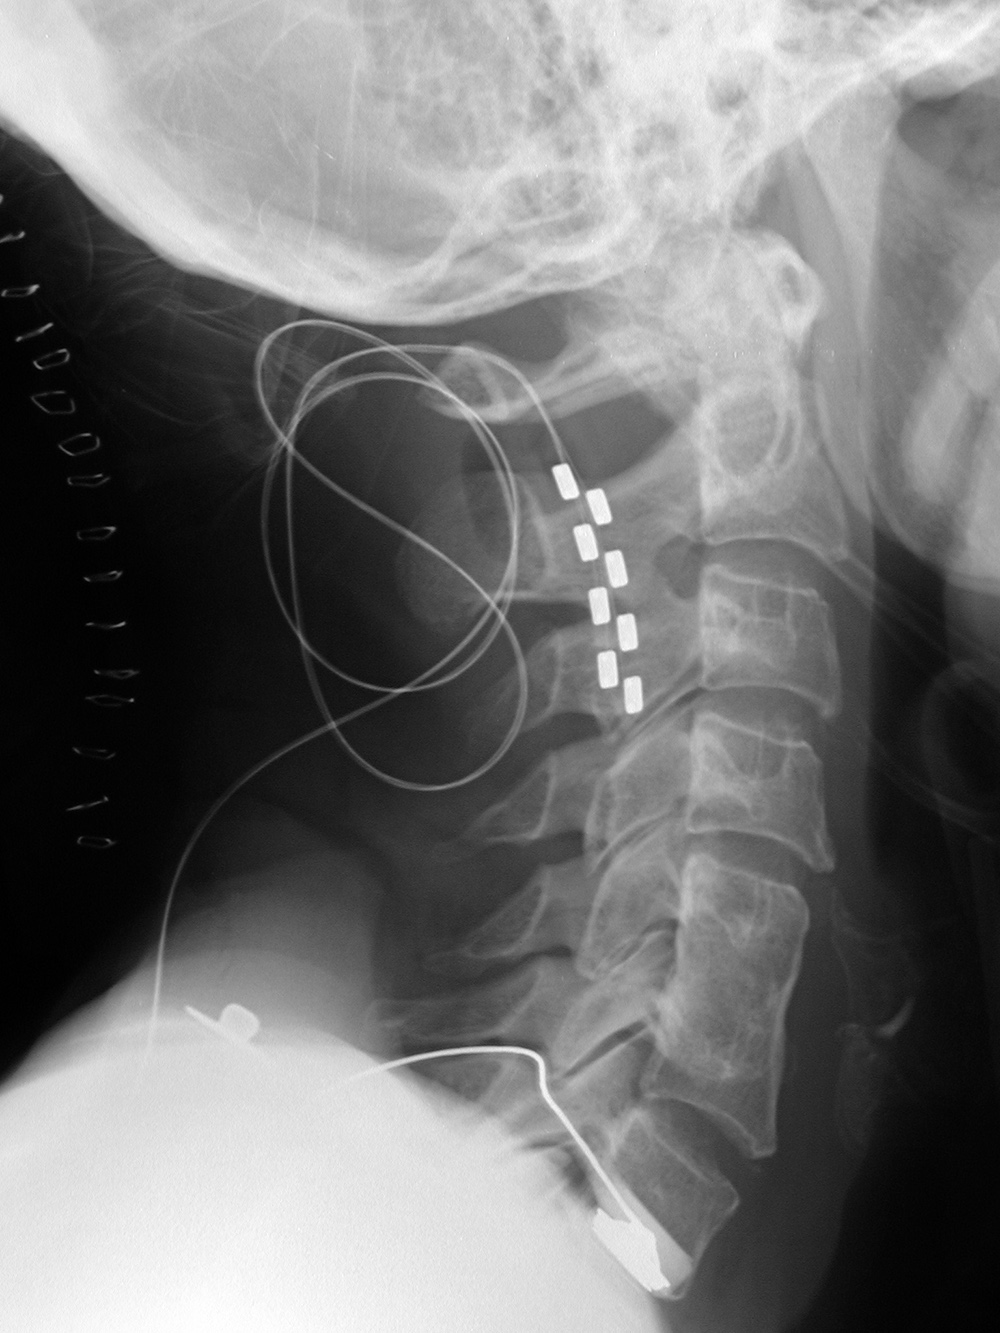

| Lateral radiograph of the neck shows a recently placed dorsal column stimulator, a nasogastric tube (black *),and an endotracheal tube (white *). |

| A left vagus nerve stimulator was placed to treat intractable epilepsy. From Hunter, 2004 |

Also shown is an anterior cervical spine fusion plate, a monitoring electrode over an ear, and a dental bridge. From Hunter, 2004 |